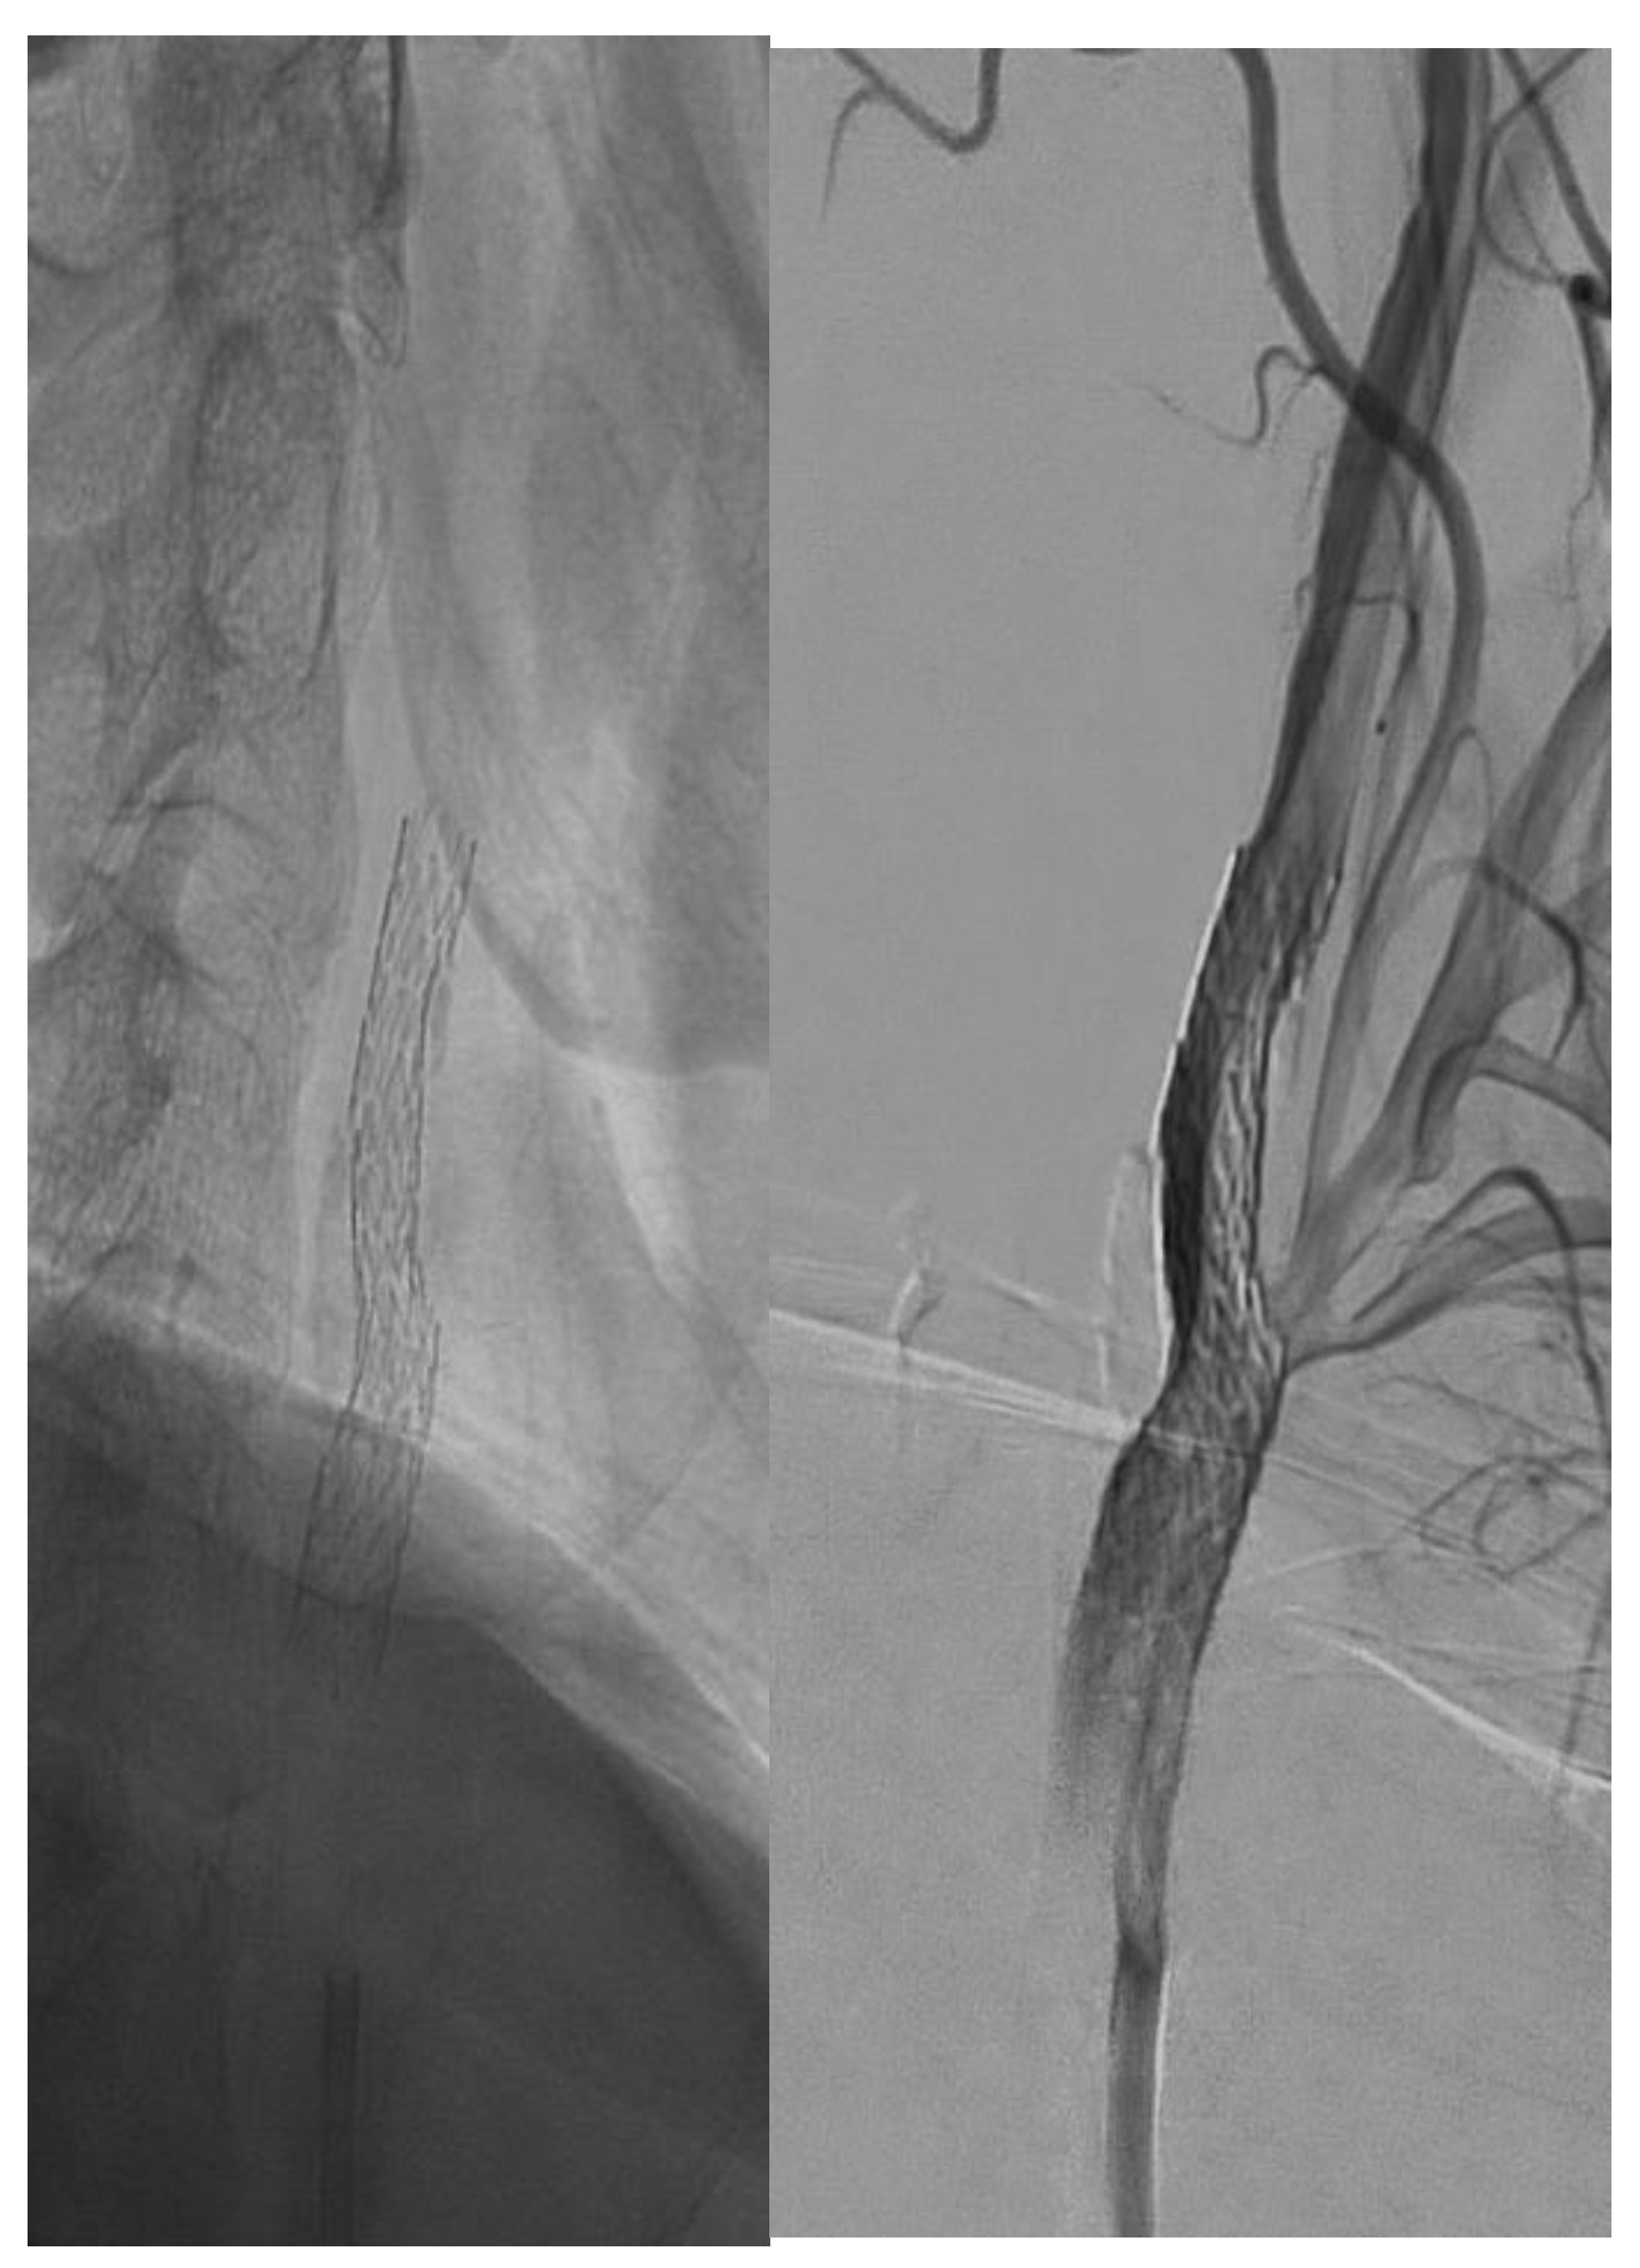

Visual differences between single- and double-layer carotid stents as seen during the angiography procedure are illustrated in Figure 2, Figure 3 and Figure 4.

Figure 1. Single-layer micromesh stent (Wallstent-Boston Scientific).

Jcm 14 00888 g001